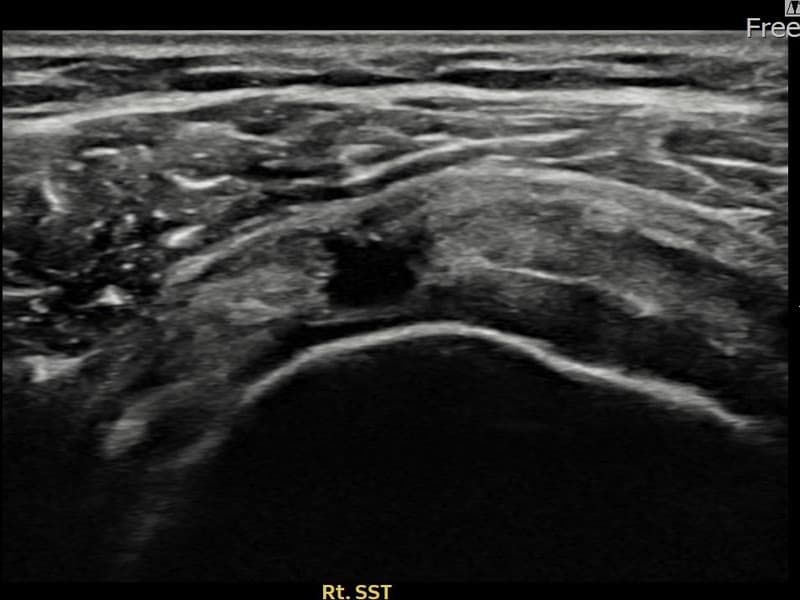

术前

术前超声确认右侧 冈上肌腱 关节面侧撕裂进展型,右侧冈上肌腱回声不连续伴肌腱缺损(12mm × 7mm (肌腱厚度约55%缺损))。术后超声显示撕裂部位充满再生组织,肌腱连续性恢复,回声模式正常化。